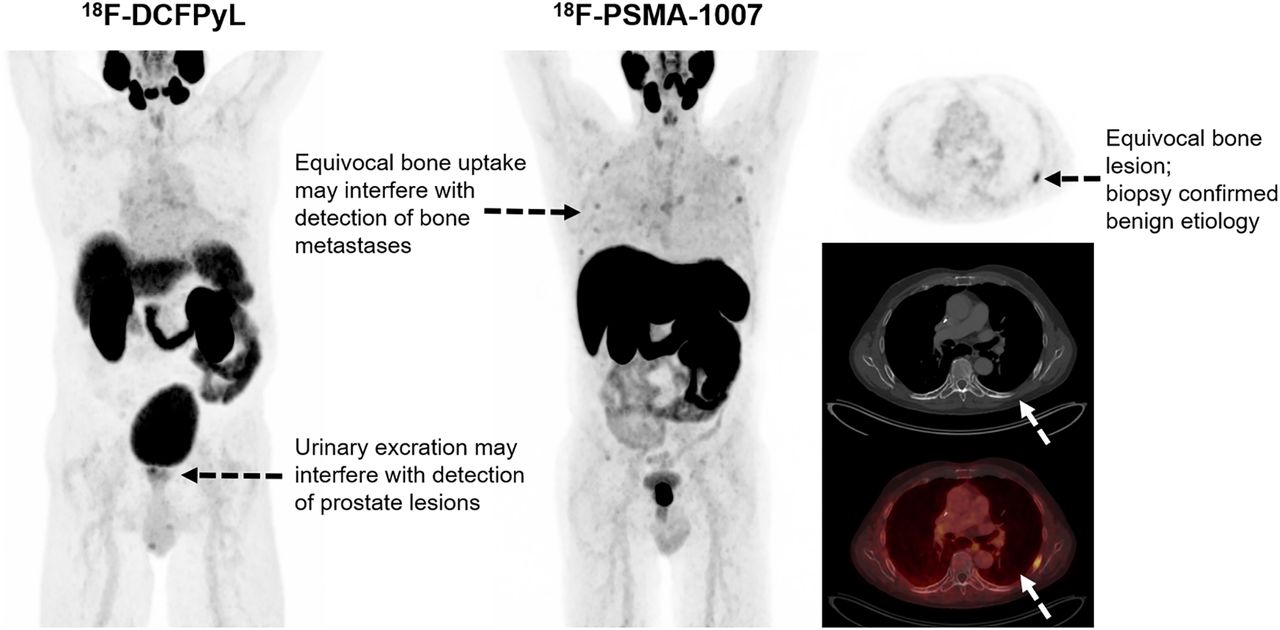

Matched-Pair Comparison of 18F-DCFPyL PET/CT and 18F-PSMA-1007 PET